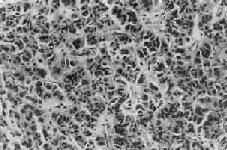

1.胰岛的病变不同类型的糖尿病及其不同时期,病变差异甚大。Ⅰ型糖尿病早期可见胰岛炎,胰岛内及其周围有大量淋巴细胞浸润,偶见嗜酸性粒细胞。胰岛细胞进行性破坏、消失,胰岛内A细胞相对增多,进而胰岛变小,数目也减少,有的胰岛纤维化;Ⅱ型糖尿病用常规方法检查时,早期几无变化,以后可见胰岛B细胞有所减少。常见变化为胰岛淀粉样变,在B细胞周围及毛细血管间有淀粉样物质沉着(图15-18),该物质可能是胰岛素B链的分解产物。

图15-18 糖尿病之胰岛

图示胰岛淀粉样变